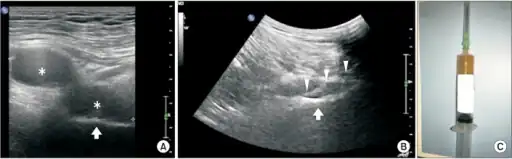

- High-frequency ultrasonography to identify the location of pudendal nerve compression.

- Doppler ultra sound to detect vein compression, a result of nerve compression.[25]